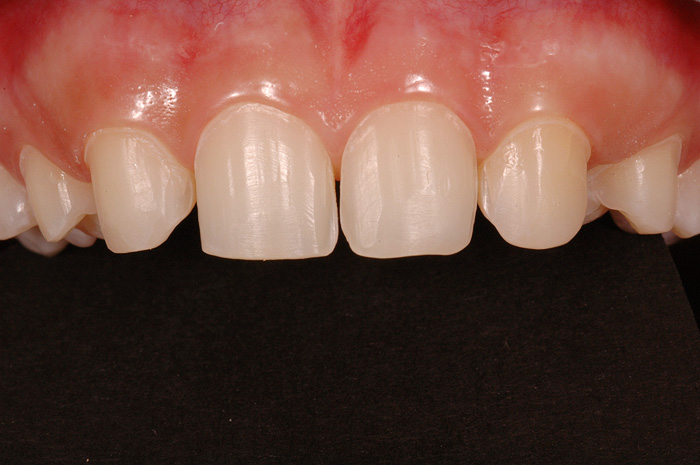

Fallbeispiel

Zum Vergrössern klicken